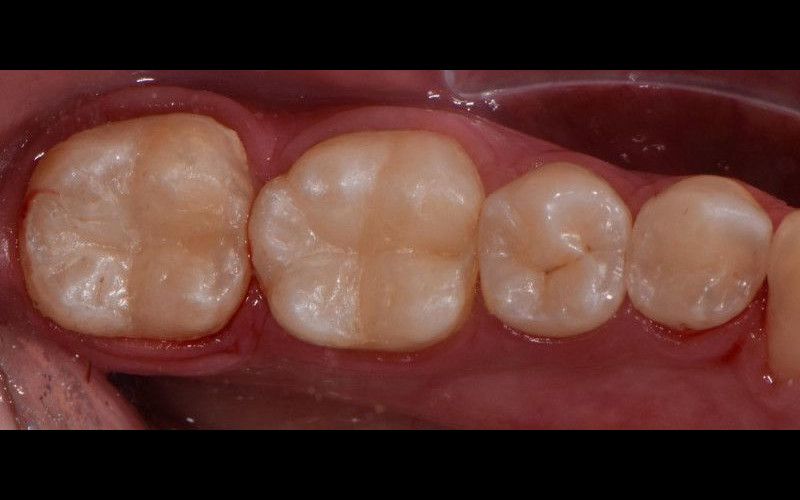

Anestesiamos con técnicas indoloras, que nos permite la endodoncia. Consiste en eliminar el tejido pulpar dañado, permitiendo posteriormente rehabilitar el diente, mediante técnicas especiales, donde usamos postes de fibra de vidrio, composites especiales para la reconstrucción de muñones, incrustaciones y coronas, que permiten conservar el diente, devolviéndole su funcionalidad tanto estética como masticatoria.

• Y dejamos preparado el diente para su rehabilitación posterior que se realizará lo más pronto posible.

No hay mejor prótesis que mantener nuestros propios dientes en boca. Mejoran con creces en funcionalidad y estética cualquier implante o prótesis colocada.

Su tasa de éxito es exactamente la misma que la de implantes, y no sólo eso, sino que conserva el hueso alrededor del diente, además de darnos sensibilidad a la masticación y una estética y funcionalidad perfectas.